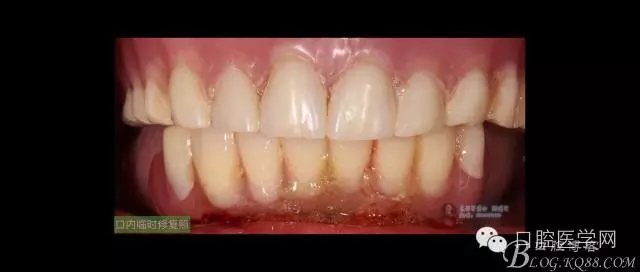

ICX-ON-4即刻負(fù)重